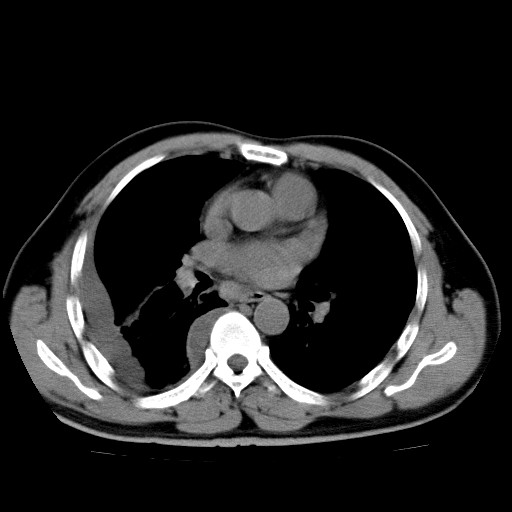

男,54岁,咳嗽,右侧胸痛10天。肺窗>150k,传不了

右中央型肺癌并右肺下叶不张,纵隔内及右胸膜转移,右胸腔积液

考虑   右肺癌伴右下肺部分不张,阻塞性肺炎,纵隔淋巴结增大,右侧胸腔积液其他待排

右下叶大片实变,肺门未见明显肿块影。有胸腔积液和纵隔内肿大淋巴结影。没有增强和肺窗,不好定。

考虑:1、右下叶周围型肺癌伴胸膜、纵隔淋巴转移?

右下叶大片性阻塞性肺炎,肺门未见明显肿块影,纵隔内可见肿大淋巴结影,右见右侧胸腔积液及右侧胸膜增厚。

考虑:右侧中心性肺癌?伴纵隔淋巴结转移。建议上传肺窗。